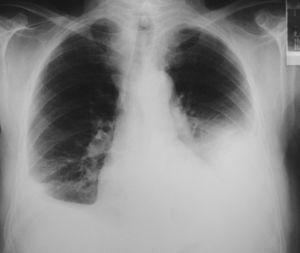

A los 18 meses del diagnóstico el paciente mejoró de una forma muy discreta su clase funcional y no había presentado nuevos episodios de isquemia coronaria. La radiografía de tórax reflejaba la persistencia de una paquipleuritis bilateral de predominio izquierdo (fig. 3). En el estudio funcional respiratorio la capacidad vital forzada era de 1,87 l (41%), volumen espiratorio forzado en el primer segundo de 1,28 l (40%), cociente de ambos parámetros del 69%, volumen residual del 70% y capacidad pulmonar total del 56%; en la gasometría arterial basal el pH era de 7,43, presión arterial de oxígeno de 73,5 mmHg y presión arterial de anhídrido carbónico de 40 mmHg.

Fig. 3. Radiografía de tórax a los 18 meses de seguimiento. Paquipleuritis bilateral de predominio izquierdo.